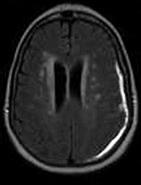

- 单项选择题女,71岁, 头晕,言语模糊, 2周前被摩托车撞伤,结合MRI图像选择最可能的诊断 ( )

D、亚急性硬膜下血肿

E、慢性硬膜下血肿